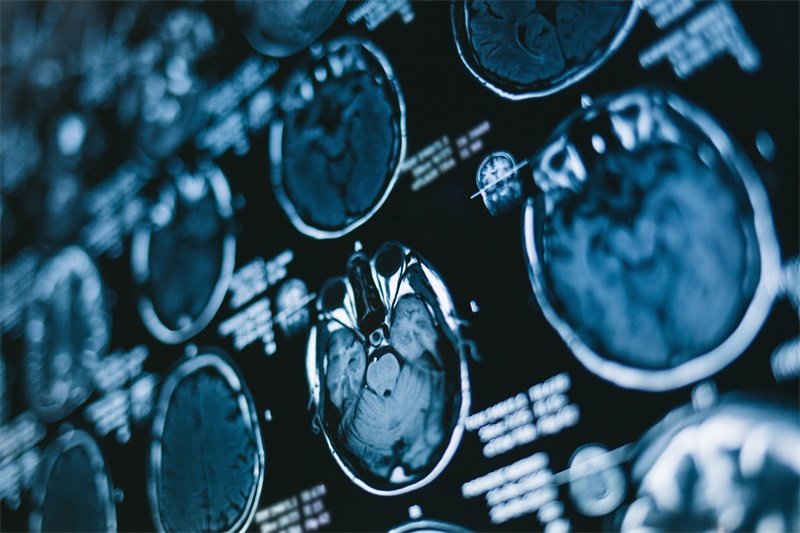

磁共振成像(MRI)和计算机断层扫描(CT)是常用的初步筛查方法。

这些影像学检查能够提供清晰的脑部结构图像,帮助医生评估病变的大小、性质以及对周围结构的影响。